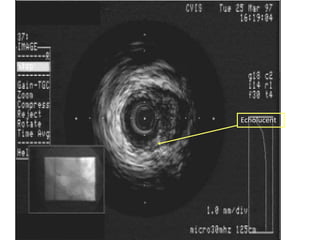

IVUS Technology

• Real time high resolution imaging.

• 2D tomographic assessments of vessels

Also longitudinal and 3D computer asssited

reconstruction.

• Allows assessment of total vessel lumen and

plaque dimension in vivo.